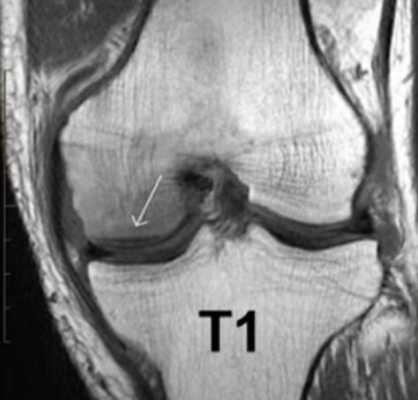

МР-скан коленного сустава в Т1 режиме (стрелкой указан костный отек)

В структуру сочленения входит множество мелких элементов. Правильно прочитать томограммы сможет специалист в области рентгенологии с внушительным практическим опытом. В спорных ситуациях результаты МРТ предоставляют для чтения нескольким врачам. Человек без медицинского образования и соответствующих навыков не сможет расшифровать снимки. Чтобы понять заключение рентгенолога, требуются глубокие знания. По этой причине трактовку результатов МР-томографии лучше доверить врачу (травматологу или ортопеду).